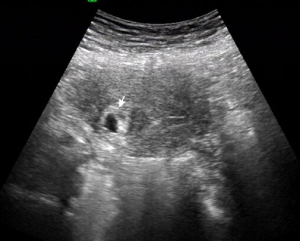

孕卵在子宮腔角部、鄰近輸卵管開口處發育,胚胎組織在宮腔內,稱為宮角妊娠。很少見。如早孕時發生流產,常有大出血,如達足月可隨時發生子宮破裂,產後胎盤不易剝離,可致大出血,危及產婦生命。早孕時常有下腹痛。婦科檢查在子宮的一側角部明顯突起,囊性,有壓痛,B超檢查胎兒在宮腔內。早孕行人流吸宮,僅吸出蛻膜而無絨毛,或術後突然腹痛,面色蒼白有休克或內出血徵象;中期或晚期妊娠時,常訴子宮底的一側腹痛,或無原因突然發生全腹劇烈疼痛,內出血,顯示有子宮破裂體徵;產後胎盤不剝離伴出血,行人工剝離時感胎盤附著處很高,且偏向子宮側角部,用力剝時可發生劇烈腹痛及大出血。如在妊娠早期明確診斷為宮角妊娠,胚胎存活,圓韌帶向外側移位,覆蓋在胚囊的子宮肌層組織健康,可不考慮終止妊娠,繼續隨訪觀察。如有急性破裂現象應開腹手術。

宮角